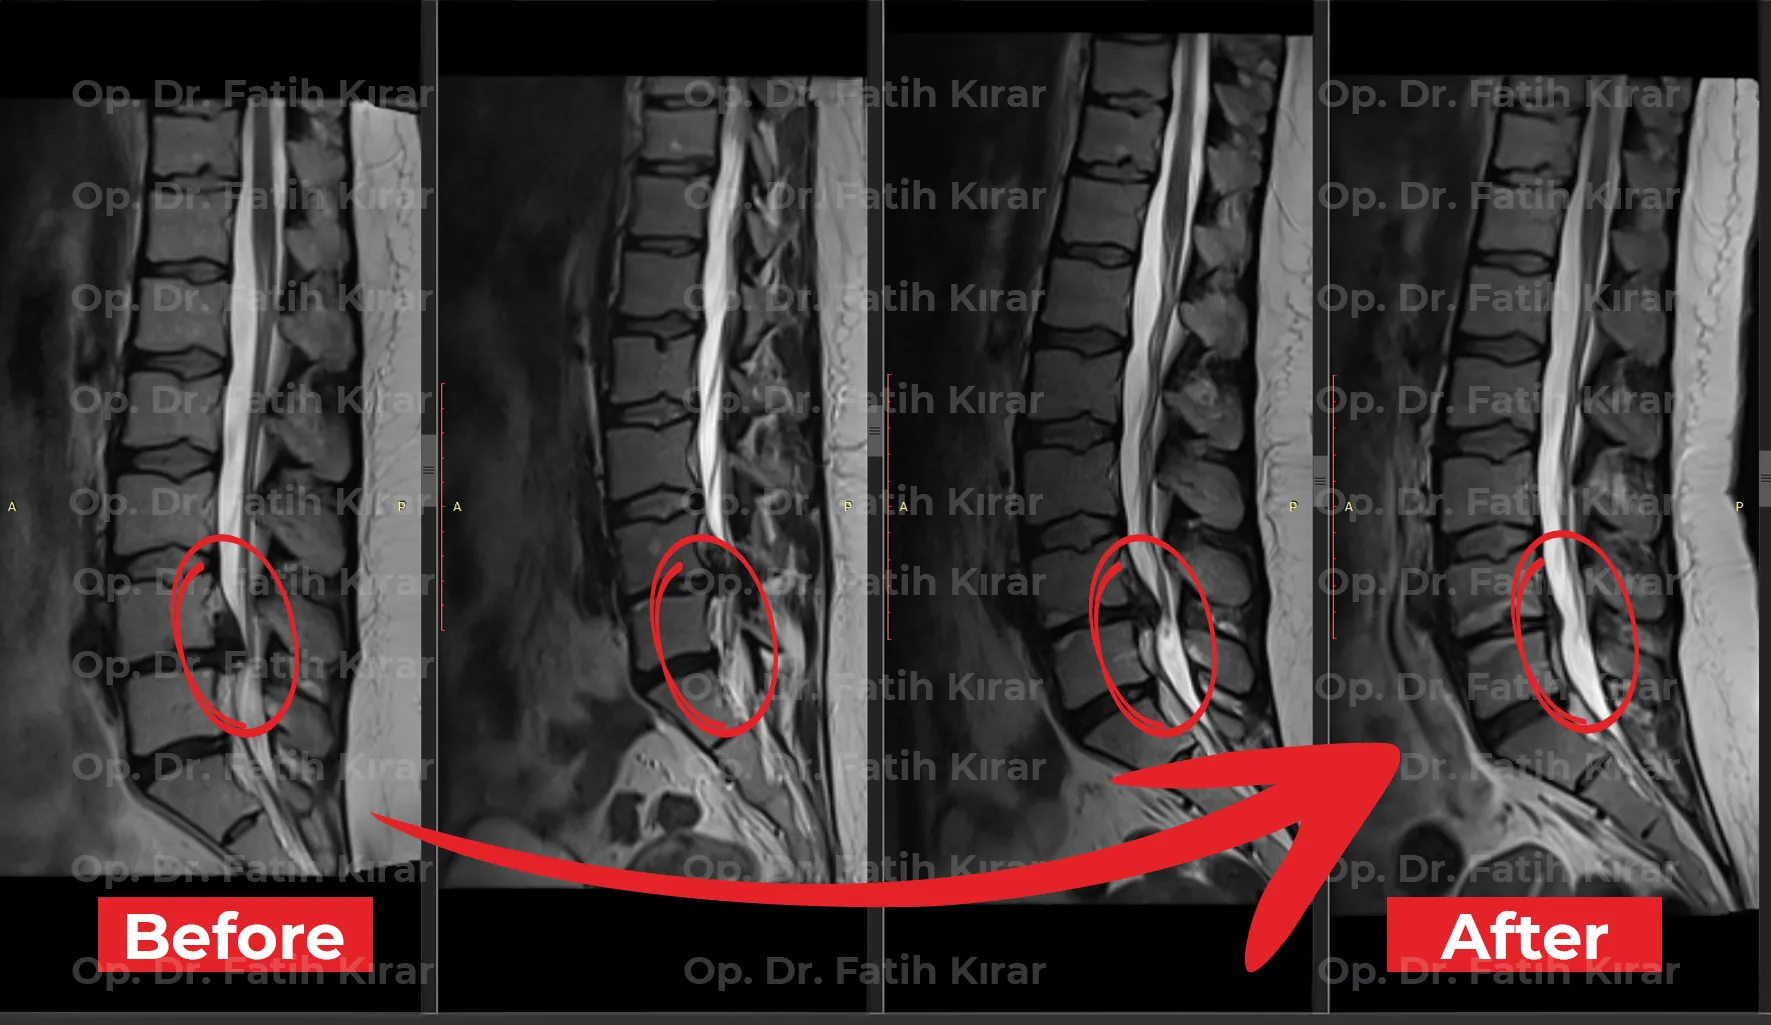

Advanced minimally invasive and non-surgical interventions with proven outcomes. MRI results demonstrating successful treatment of spinal conditions.

Spinal intervention MRI - Pre and post treatment